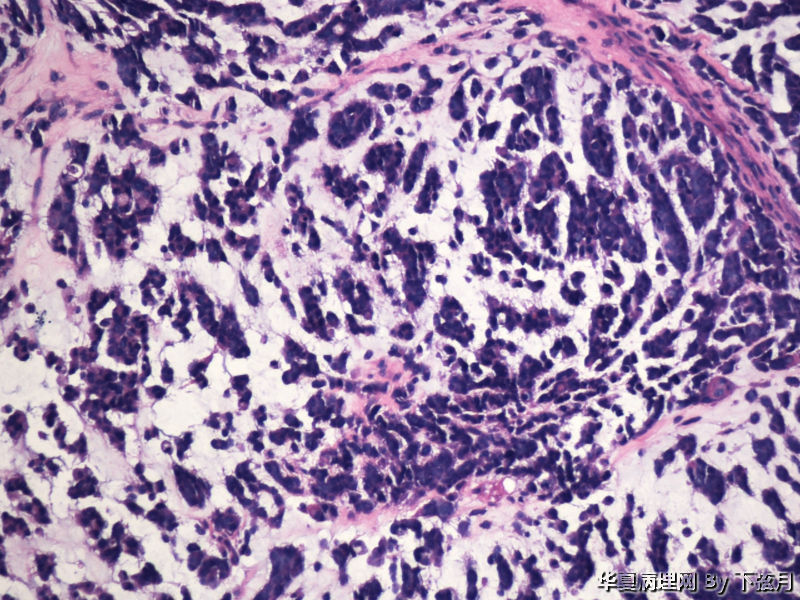

左侧颞叶及胼胝体膝部占位图4

名称:图4

描述:HE 100-3

This enhancing lesion with GFAP positive cells and should consider some type of glioma, probably high-grade.

丰富黏液背景,漂浮乳头状或簇状分布的瘤细胞,免疫组化GFAP,S-100阳性。

有血管轴乳头,粘液样物中漂浮的细胞呈团块状和小乳头状。支持粘液型乳头状室管膜瘤。